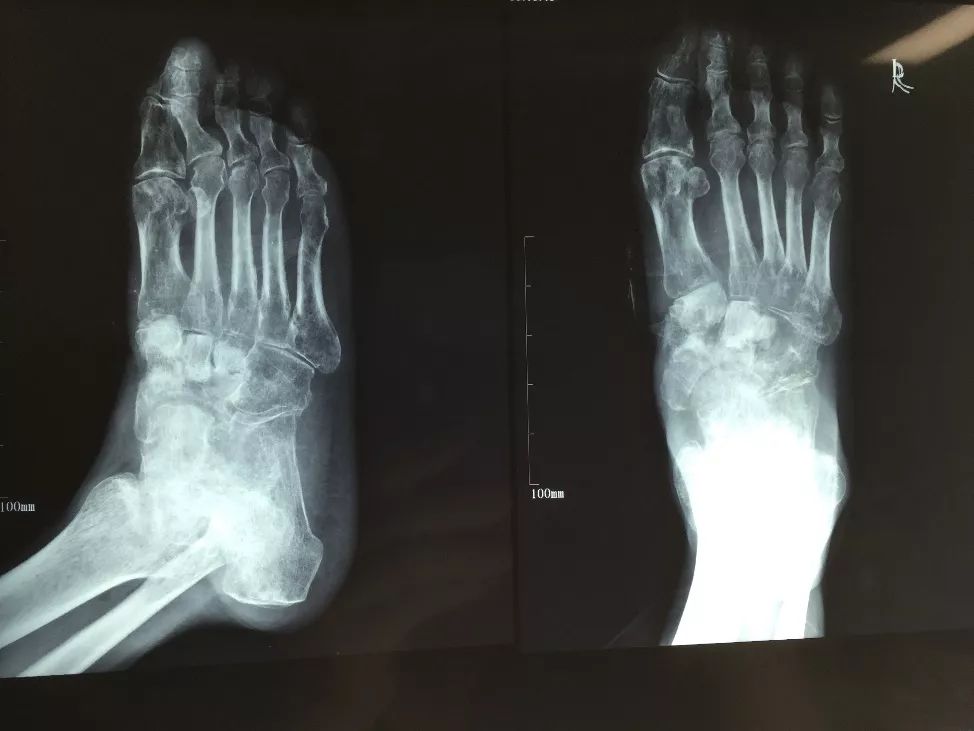

患者,男,56岁,脑外伤及下肢开放伤,急诊手术未使用双氧水,生理盐水冲洗伤口,外固定架固定,伤口游离植皮闭合。骨折及伤口获良好愈合

化繁为简固定法

• 按照多段骨折化繁为简固定方式复位固定近端骨折实现闭合处理。

• 创面新鲜后植游离皮

• 尽快下地走路,生理应力促进骨愈合

• 近端3个月愈合,远端用8个月

• 而后去除外固定架

• 如果使用双氧水会造成骨膜破坏,骨坏死外露,而后骨缺损,需要皮瓣植骨或骨搬运。